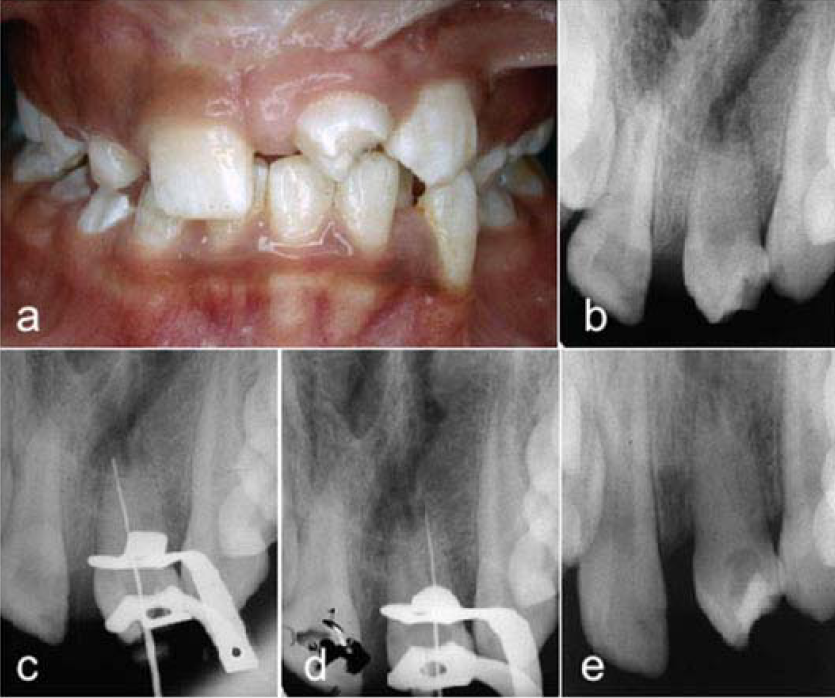

Indivíduo do gênero feminino de 11 anos de idade, com fissura pré-forame incisivo unilateral completa, matriculada no Hospital de Reabilitação de Anomalias Craniofaciais da Universidade de São Paulo (HRAC/USP), apresentava o pré-molar inferior esquerdo transplantado na posição do incisivo central superior esquerdo (Fig. 1, a), extraído anteriormente devido a processo de reabsorção externa avançado. A história clínica revelou que após 2 meses da realização do transplante dentário autógeno, a paciente referenciou dor espontânea no dente transplantado, sendo necessária a avaliação endodôntica. A radiografia de diagnóstico foi realizada com o aparelho radiográfico Dabi Atlante modelo Spectro 70X (Dabi Atlante Ind. São Paulo, Brasil) (Fig. 1, b), onde se observou imagem sugestiva de lesão periapical e ao teste de sensibilidade realizado com Endo-Ice (Coltène/Whaledent Inc., Langenau, Alemanha) houve resposta negativa, confirmando a necessidade da intervenção endodôntica. Após o bloqueio anestésico troncular e isolamento absoluto com lençol de borracha Hygenic Dental Dam (Coltène/Whaledent Inc., Langenau, Alemanha) e grampo 00 (SS White Artigos dentários Ltda, Rio de Janeiro, Brasil) foi realizado o acesso à câmara pulpar utilizando-se a broca diamantada no 1014 (KG Sorensen Ind. Com. Ltda, Barueri, Brasil); a forma de contorno e o desgaste compensatório das paredes foram realizados com a broca diamantada tronco-cônica de ponta inativa no 3082 (KG Sorensen Ind. Com. Ltda, Barueri, Brasil). Foram identificados dois canais um mesial e um distal, sendo a exploração inicial realizada com limas tipo K (Dentsply Maillefer, Ballaigues, Suiça) de pequeno diâmetro, em seguida foi realizada irrigação dos canais radiculares com hipoclorito de sódio (NaOCl) a 2,5 %.

a) Pré-molar inferior esquerdo transplantado na posição do incisivo central superior esquerdo. b) Radiografia de diagnóstico pré-molar inferior esquerdo transplantado na posição do incisivo central superior esquerdo. c) Confirmação da odontometria canal mesial. d) Confirmação da odontometria canal distal. e) Colocação da medicação Intracanal.

Para o preparo biomecânico dos canais radiculares, foi selecionada a técnica de Oregon Modificada, o instrumento inicial ajustado na embocadura dos canais foi a lima tipo K 55, na sequência foram utilizadas as limas tipo K 50, 45, 40, em seguida foram empregadas as brocas Gates Glidden (Dentsply, Maillefer, Ballaigues, Suiça) no 2 e 3, irrigação com hipoclorito de sódio (NaOCl) a 2,5 % a cada troca de instrumento. A seguir, foram determinados os comprimentos de trabalho com auxílio do localizador foraminal Root ZX (J. Morita, Tokyo, Japan) confirmados com a radiografia periapical para cada conduto (Fig. 1, c, d) e com a lima K 15 foi realizado o desbridamento foraminal.